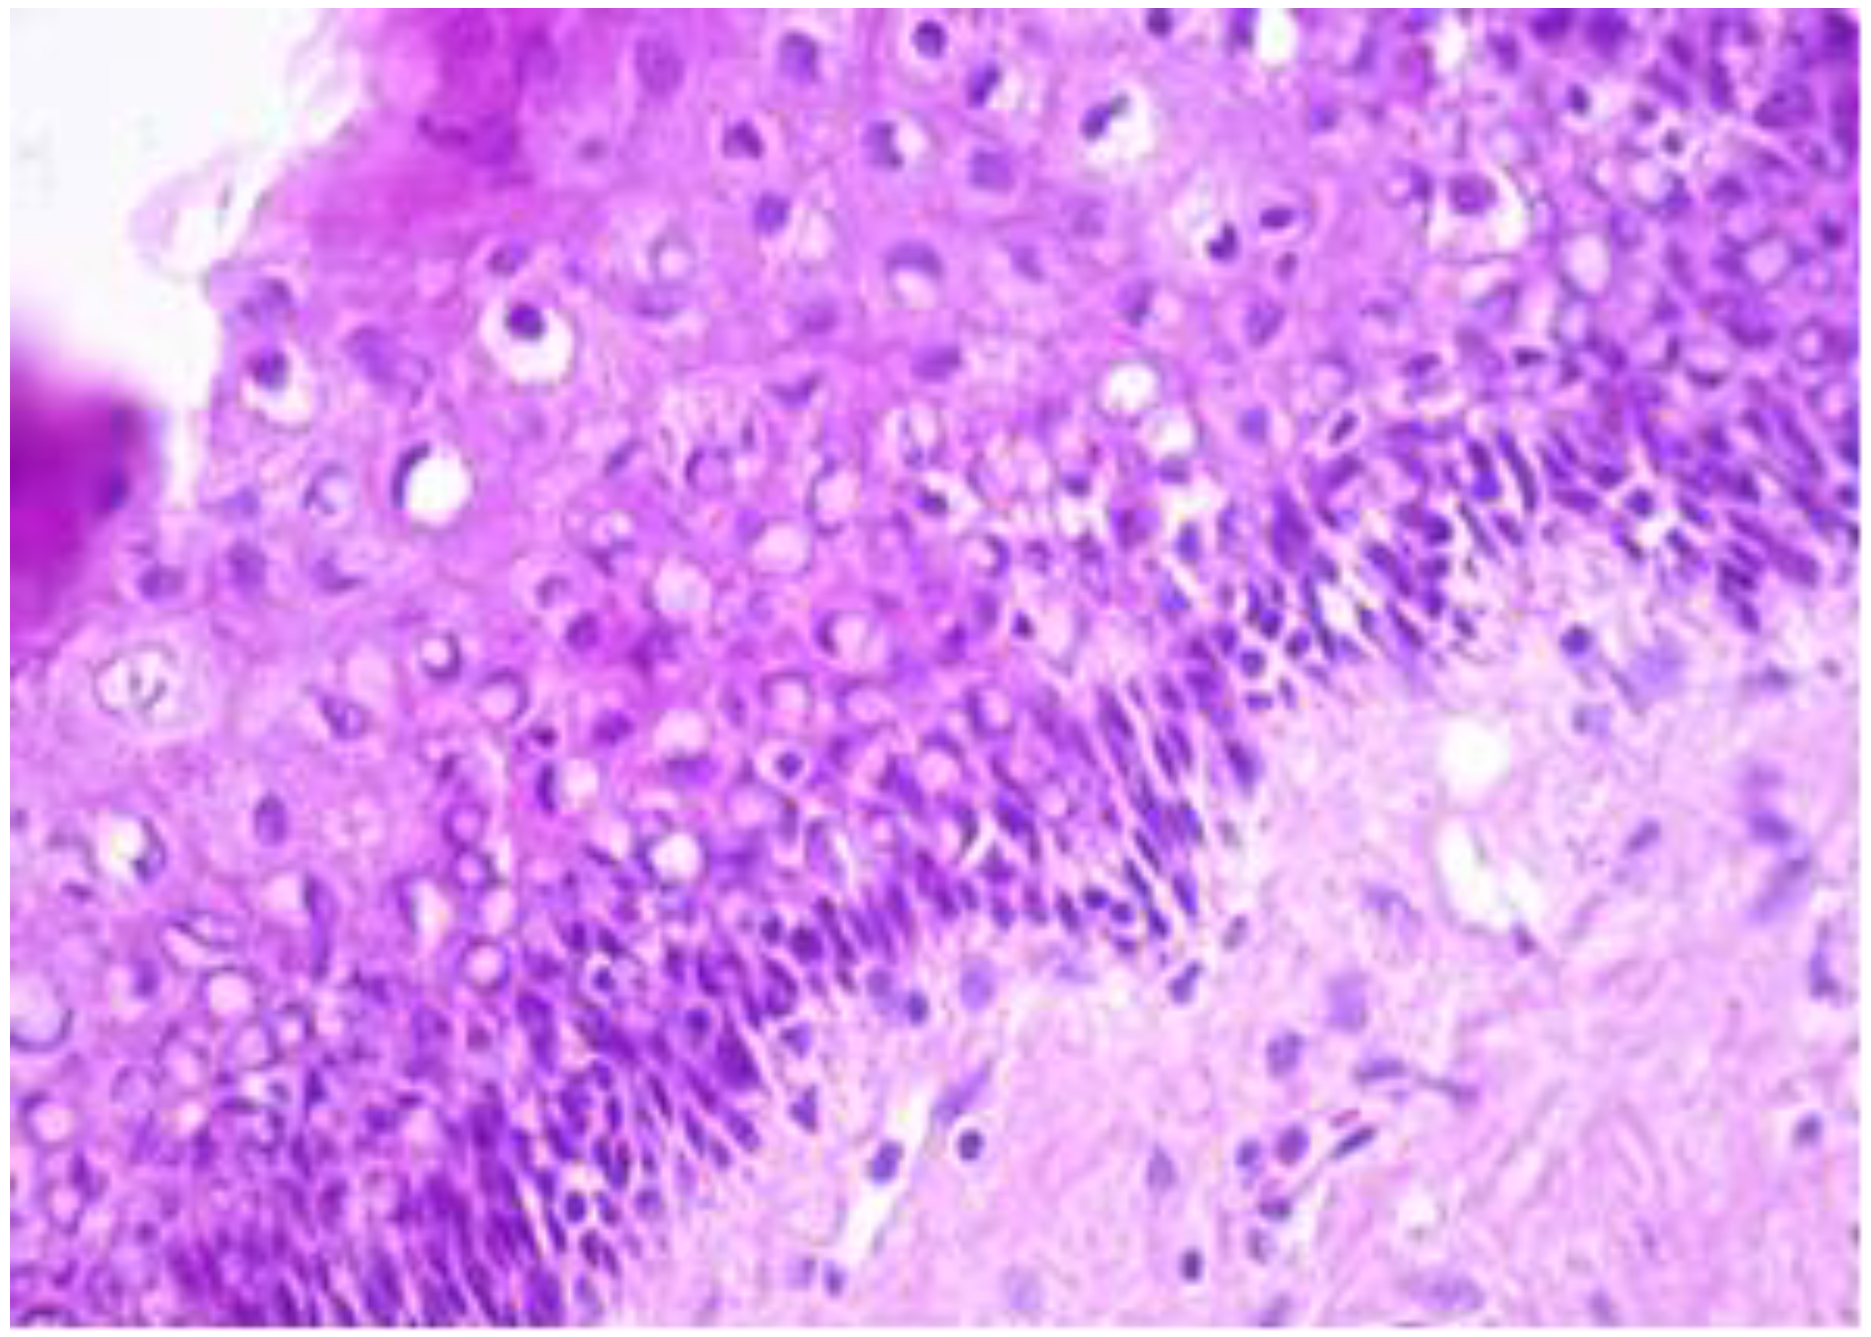

The exo-cervix was found to be lined by a non-keratinised stratified epithelium (squamous epithelium) showing a distinct basal layer, but the appearance of atypical keratinocytes was noted, with some of them showing koilocytotic atypia with sharply outlined perinuclear vacuoles, dense and irregular staining peripheral cytoplasm and an enlarged, modified nucleus (Figure 1). The p16 expression showed a positive nuclear/cytoplasmic expression in the cervical mucosa (Figure 2).

Figure 1.

Exo-cervix showing a distinct basal layer and atypical keratinocytes (HE staining, 40×).